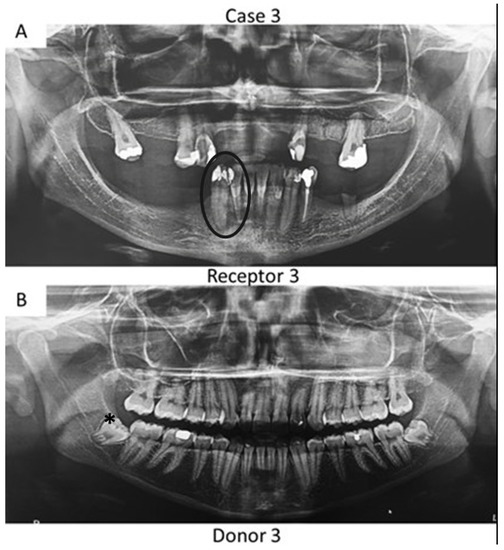

Figure 3. Panoramic radiographs of initial visit of the further two patients. Black circle indicates the teeth requiring root canal treatment (receptor teeth: lateral incisor and canine) in the mother whilst the asterisk highlights the third molar from the daughter demanding extraction (pulp donator tooth). The pulp from the donator tooth was sliced to obtain a mesial portion, which was transplanted to the lateral incisor of the mother; meanwhile, the distal part of the pulp was inserted into the mother’s canine.

Herein, the primary teeth extracted (asterisks in Figure 1 and Figure 2) were scheduled to be extracted with minimal injury as they were vertically inclined, and permanent teeth were already formed/erupted in cases 1 and 2. Furthermore, the tooth must be stored as soon as possible in a sterilized saline solution; the complete disinfection prior to pulp removal and transplantation is mandatory [21]. The sectioning of the extracted tooth must be performed using a sterilized handpiece and diamond disks only after the root canal instrumentation of the receptor tooth [10]. Pulp should also be removed with sterilized tweezers (Figure 4B) and inserted into the roots of the acceptor teeth using disinfected gutta-percha cones. Indeed, all these procedures may promote minimal contamination during the clinical treatment, thereby increasing the probability to perform bacterial-free endodontic regeneration.